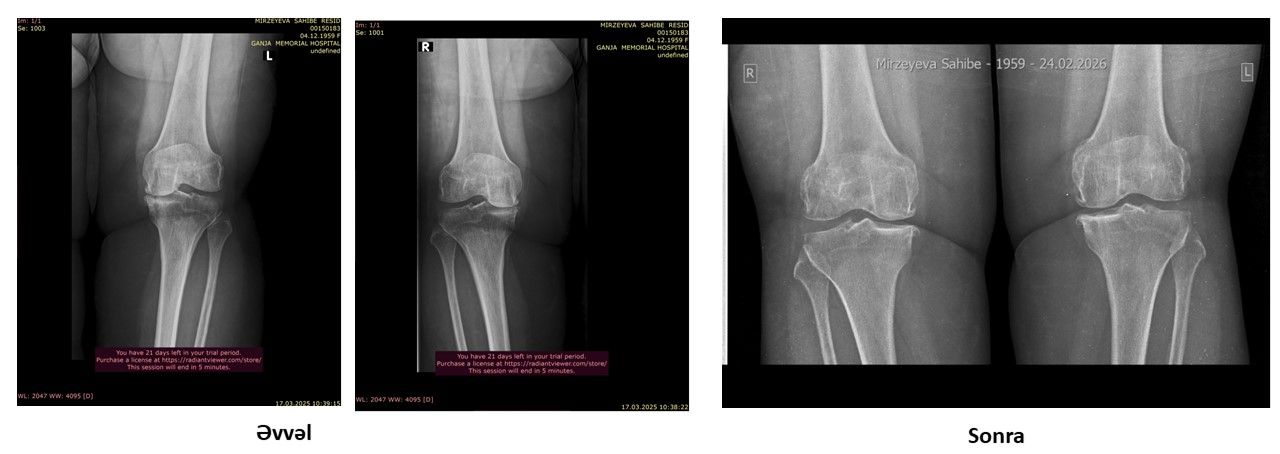

Protez təklif edildi, amma əməliyyatsız sağaldı –  Real pasiyent hekayəsi-VİDEO

Oynaqlarda yaranan artroz, xüsusilə də xəstəliyin 4-cü mərhələsi, tibbdə ən ağır vəziyyətlərdən biri hesab olunur. Bu mərhələdə xəstələrə əksər hallarda yeganə çıxış yolu kimi cərrahi əməliyyat – süni oynaq (protez) təklif edilir.

Lakin son illər bəzi klinikalarda tətbiq olunan inteqrativ yanaşmalar bu sahədə fərqli nəticələrin mümkün olduğunu göstərir.

Bioloji Təbabət İnteqrativ Müalicə Mərkəzinə müraciət edən pasiyentə 4-cü dərəcəli artroz diaqnozu qoyulmuşdu.

Pasiyent daha əvvəl müraciət etdiyi tibb müəssisələrində yalnız əməliyyatın mümkün çıxış yolu olduğu barədə məlumat almışdı. Güclü ağrılar, hərəkət məhdudiyyəti və gündəlik həyat keyfiyyətinin aşağı düşməsi onun əsas şikayətləri idi.

Nəticə: əməliyyata ehtiyac qalmadı

Aparılan müalicədən sonra pasiyentdə nəzərəçarpacaq müsbət dəyişikliklər müşahidə olunub:

• ağrılar əhəmiyyətli dərəcədə azalıb

• oynağın hərəkət qabiliyyəti yaxşılaşıb

• gündəlik fəaliyyətlər daha rahat icra olunmağa başlayıb

• həyat keyfiyyəti yüksəlib

Hazırkı vəziyyətdə pasiyent üçün cərrahi müdaxiləyə ehtiyac qalmadığı bildirilir.